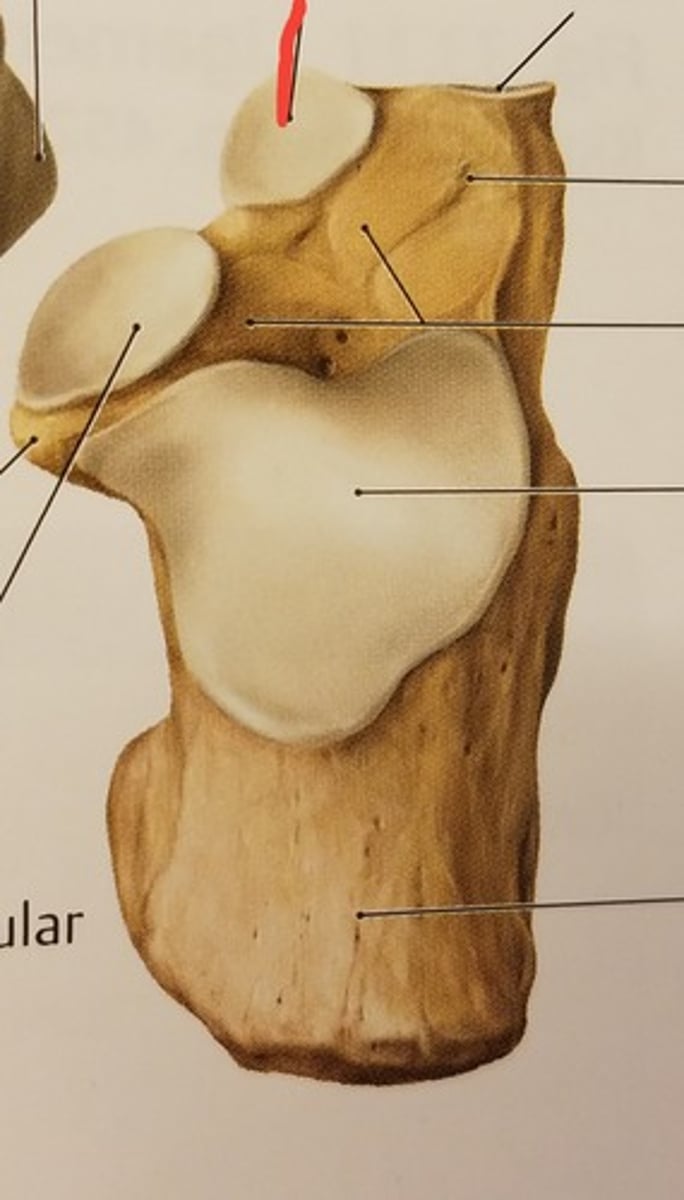

Patella

Apex

inferior surface for patellar ligament

Base

superior surface for quadriceps tendon

Medial articular surface (for medial condyle of femur; smaller)

green

Lateral articular surface (for lateral condyle of femur; bigger)

green